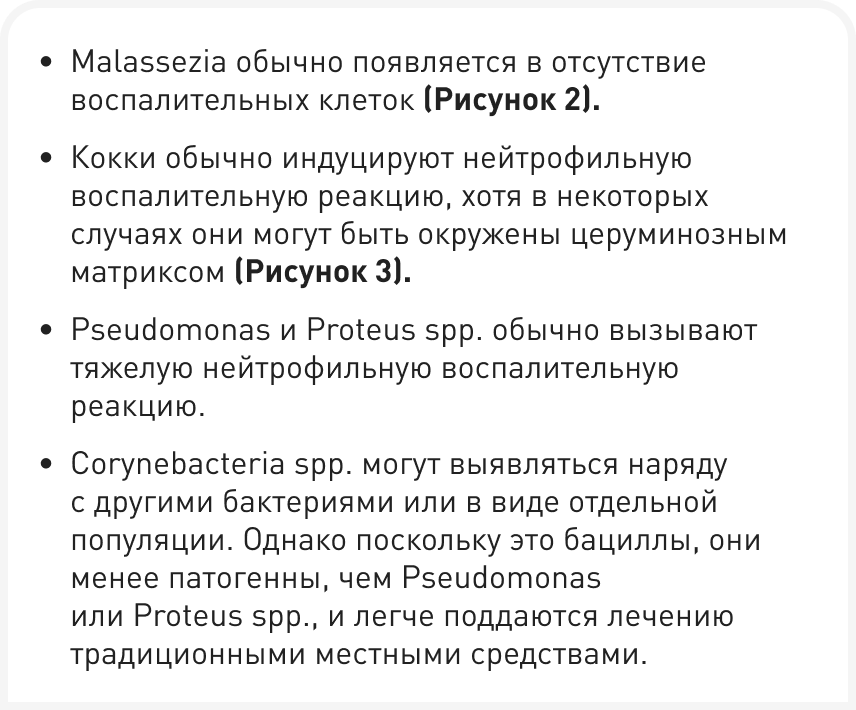

Однако не все случаи отита обязательно приводят к дисбиозу, а в некоторых ситуациях за отит можно принять обильное выделение ушной серы и зуд. Кроме того, цитологические исследования показывают, что нарушение защитных свойств и регуляции микробиома уха приводит к размножению вторичных возбудителей (Рисунки 2 и 3) (5, 6); во всех случаях отита для установления точного диагноза необходимо провести цитологическое исследование, и некоторые советы приведены в Таблице 1.